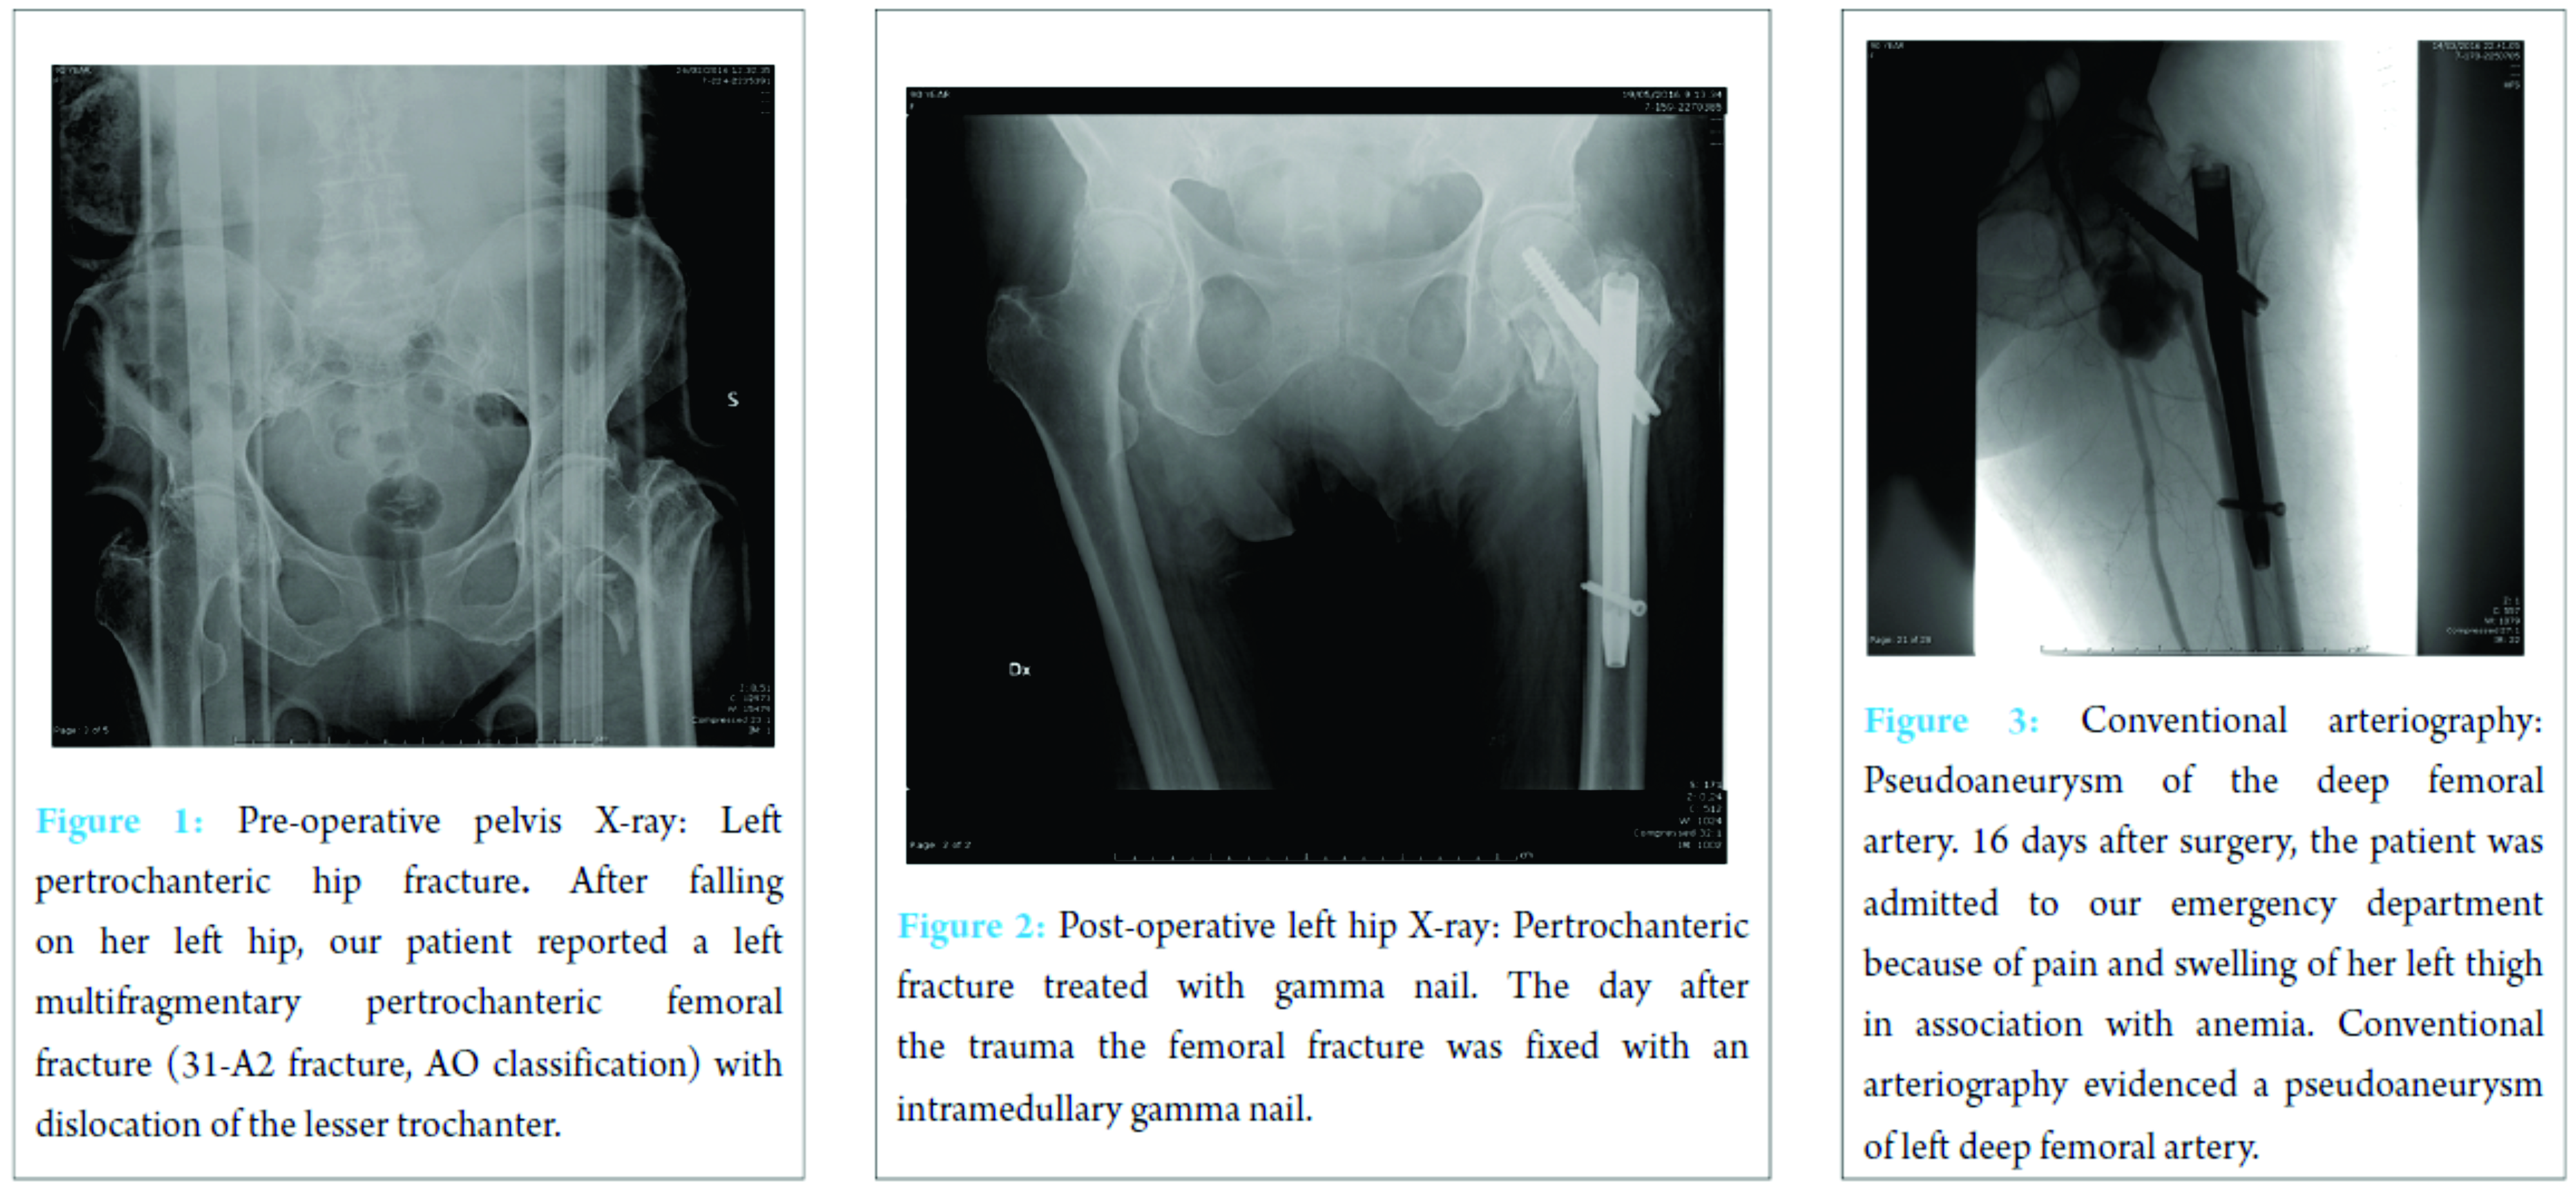

A 90-year-old female was admitted to our emergency department after falling on her left hip. On physical examination, the patient’s left leg was painful, shorter, and in external rotation. The patient was completely unable to bear any weight on it. A radiograph of her hips and pelvis showed a left multifragmentary pertrochanteric femoral fracture (31-A2 fracture, AO Classification) with dislocation of the lesser trochanter (Fig. 1).

The day after, the fracture was fixed by means of an intramedullary nail without perioperative complications (Fig. 2). The post-operative course was regular apart from mild post-surgical anemia on the second post-operative day that was treated with two blood transfusions. On the 5th post-operative day, general conditions of the patient were good and the surgical wound had no signs of infection and no exudate, so she was discharged. 16 days after discharge, the patient made a new access to our emergency department for the appearance of severe anemia, pain, and swelling of her left hip. First of all, Doppler ultrasound was performed, and a large pseudoaneurysm of the proximal part of the profunda femoris artery was found. Her hemoglobin value was 7.7 g/dL, so she was urgently transfused. Then, left lower extremity arteriogram was performed and confirmed the diagnosis (Fig. 3).

Therefore, a stent was placed (Fig. 4). After this procedure, the clinical conditions improved and the patient was discharged 4 days later with stable blood exams. On the last clinical control, 3 months after the stenting, the patient was feeling well and had started physical rehabilitation.

Hip fractures in older patients are the most common fractures treated by orthopedic surgeons. The incidence increases with age and degree of osteoporosis. The most frequent traumatic mechanism is a low energy fall from a standing height [5]. Proximal femoral fractures may be treated using different techniques of fixation. Screws or partial arthroplasty proves to be efficient for the synthesis of intracapsular fractures, whereas nails and plates are the most commonly employed for extracapsular fractures. In our case, we treated a 31-A2 fracture with a gamma nail. The role of intramedullary fixation for the treatment of this kind of fracture is still debated. Anyway, gamma nail is often preferred to slide hip screws, especially, because of easy handling instrumentarium and implant versatility. According to many authors, gamma nail has proved to be a safe and efficient fixation of pertrochanteric fractures [6]. Vascular complications after intramedullary fixation of pertrochanteric fracture are rare. These complications can develop after fracture during intramedullary hip nailing and displacing of bone fragment during fracture or repair. Furthermore, some authors suggest that manipulation of atherosclerotic vessels of the leg on the fracture table may injure their brittle endothelium with an increased risk of bleeding and thromboembolic events. Vascular injuries may be hemorrhagic or thrombotic, acute (hemorrhage), or delayed (pseudoaneurysm formation). Regardless of the type of vascular lesion, the most frequently injured vessel is the deep femoral artery followed by its perforating branches [4]. False aneurysms or pseudoaneurysms are surrounded by a thin fibrous capsule in contrast to true aneurysms that consist of the true layers of the arterial wall. The fibrin capsule is made of soft tissues and/or hematoma adjacent the vessel. There is a high risk of enlargement and rapture of the vessel, in particular, when the dimension of the pseudoaneurysm is superior to 3 cm. Rapid expansion, infection, skin or soft tissue necrosis, neuropathy, distal ischemia, pain, or rupture are the most important indications for repair [7]. The incidence of pseudoaneurysm after hip fracture is very low (0.21% of incidence) and rarely reported as a consequence of dislocated bone fragments. According to literature, arterial damages can occur because of bone spikes, tip of the screws, drills, displaced implants, and retraction of surrounding tissue [8]. In our report, X-ray imaging after surgery shows the proximal migration of lesser trochanteric fragment, due to the action of iliopsoas that fits on the lesser trochanter, near the pseudoaneurysm. According to symptoms and instrumental studies, it seems that dislocated fragment may have damaged the deep femoral artery that lies near proximal femur (Fig. 5). However, in almost 25% of pertrochanteric fracture, the lesser trochanter was involved, but vascular complications rarely occur, probably thanks to vessels elasticity. Clinical manifestations of a false aneurysm after hip fracture have been reported between 3 days and 14 years, but in cases of dislocated lesser trochanter being responsible for vascular lesion, these manifestations are more frequent between 18 and 36 days. Probably clinical appearance of the pseudoaneurysm is delayed until the patient starts mobilization that can dislocate bone fragments. In this case, we found the pseudoaneurysm 16 days after surgery, below the average reported in literature. Often it is difficult to identify this complication because of non-specific symptoms including pain, edema, and swelling that are common after hip surgery. We should suspect a pseudoaneurysm if the patient presents falling of hemoglobin level, pulsatile swelling, or venous engorgement, and we can diagnose this complication by duplex ultrasound (US), conventional angiography, and computed tomography (CT) angiography [9]. US is the method of choice for diagnosis of pseudoaneurysm with sensitivity between 94 and 97%. As in our case, conventional angiography (or CT-angiography) can be useful to confirm and to better define the vascular lesion. There are numerous treatment options for deep femoral artery pseudoaneurysm: Conservative management for smaller aneurysms, US-guided compression, percutaneous US-guided thrombin injection, percutaneous US-guided collagen injection, insertion of coils, covered stents, and open surgery [10]. The treatment we chose consisted in positioning an endovascular stent covered by polytetrafluoroethylene. After the procedure, symptoms improved and the patient was able to resume the rehabilitation program a few days later.